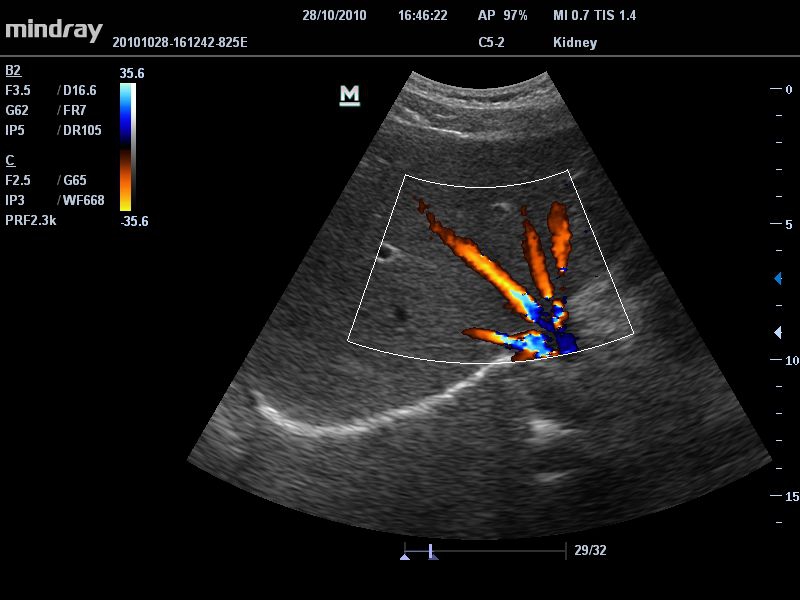

Цветовой допплер:

Да

Энергетический допплер:

• Режимы сканирования: B/M/CFM/PDI/Направленный PDI/PW, HPRF, Тканевая гармоника, М- и цветной М-режим.